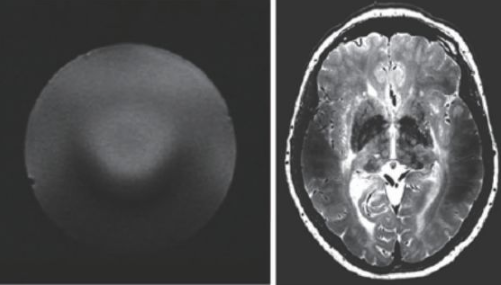

超高場(chǎng)MRI的射頻場(chǎng)設(shè)計(jì)也是一個(gè)較為困難的問題。由于射頻頻率超過了300 MHz,介電常數(shù)引起的問題非常突出。圖13 是一個(gè)在7 T 下的成像結(jié)果,可以看到在圖像內(nèi)部的信號(hào)非常不均勻,由于射頻波長(zhǎng)的極度縮短,組織的介電常數(shù)對(duì)射頻場(chǎng)的分布有極大的影響,這也是目前超高場(chǎng)MRI 需要解決的重要問題之一。目前的9.4 T以上的MRI設(shè)備還難以獲得人體體部掃描的良好圖像,其主要應(yīng)用還是做頭部的掃描。

圖13 超高場(chǎng)下的射頻場(chǎng)不均勻性